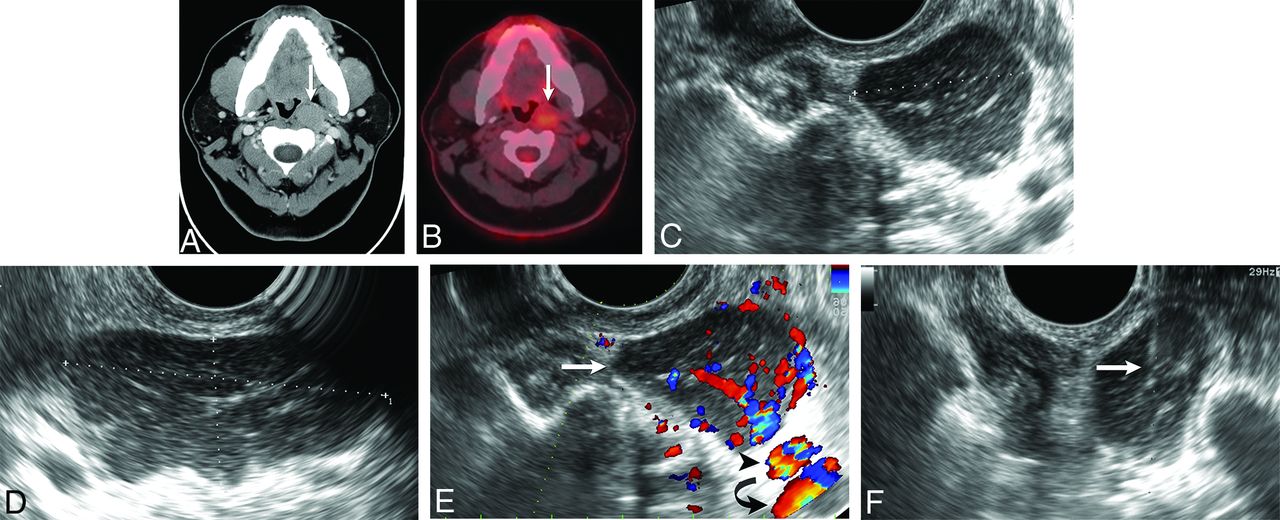

A right 3.0 × 2.0 × 1.5 cm retropharyngeal lymph node of concern was detected on staging CT in a 65-year-old man with a history of PTC. A TOUS-FNA was performed, and cytology showed metastatic PTC. The patient subsequently underwent transoral robotic resection of the lesion aided by localization with methylene blue inserted by TOUS guidance. Histology confirmed the cytologic diagnosis of metastatic PTC (Fig 3).

True-positive cytology. A 65-year-old man with a history of papillary thyroid cancer and a right retropharyngeal mass. A, Axial contrast-enhanced CT scan shows an enlarged right retropharyngeal node (arrow) with internal calcification. B, Transverse power Doppler sonography shows the lesion (arrow) and its relationship to the internal carotid artery (arrowhead) and internal jugular vein (curved arrow). C, Transverse sonography during biopsy of the mass documents placement of needle tip (white arrow) within the lesion before and during aspiration. Cytology revealed metastatic papillary thyroid cancer.